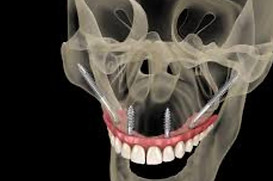

Zygomatic implants are a game-changer for patients with severe bone loss, but mastering this advanced technique requires specialized training. With so many courses available globally, choosing the right one can be challenging.